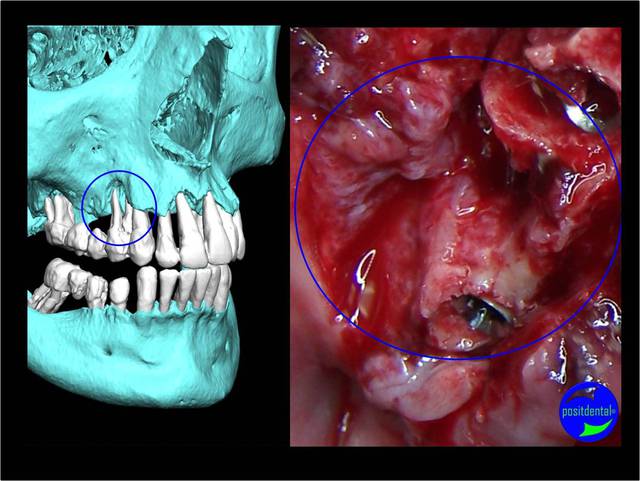

A la mandibule :

Au maxillaire , même moi qui ne suis qu'un petit , petit omnipraticien , et surtout pour le dernier à droite d'implant c'est hallucinant et avec mon expérience en bricolage , bin ce all on5 et demi me fait peur . Je ne vois pas pourquoi virer un bloc antérieur et ne pas profiter des alvéoles de chaque dent , en postérieur attendons que Pp très au fait revienne .